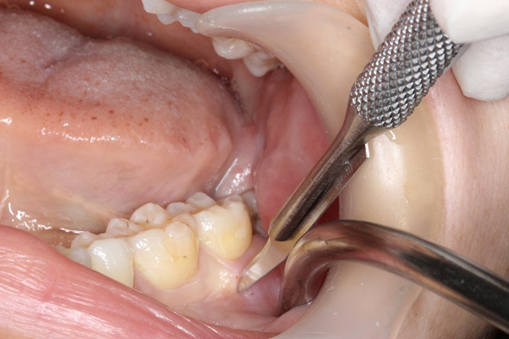

次に、歯根部分を、除去した歯冠部分のスペース方向に引っ張り出し、歯根を除去します。

すべての歯が除去できたら、歯の破片などが残っていないか最終確認をします。

切開した歯肉を縫合します。

縫合も、ただ歯肉どうしを縫うのではなく、歯肉の層がズレたり重なったりしないように糸をかけ縫合します。

この時、歯肉の層がズレたり重なったりしてしまうと、創部治癒後に7番歯周囲の歯肉炎、歯周病の進行を引き起こす原因となってしまいます。